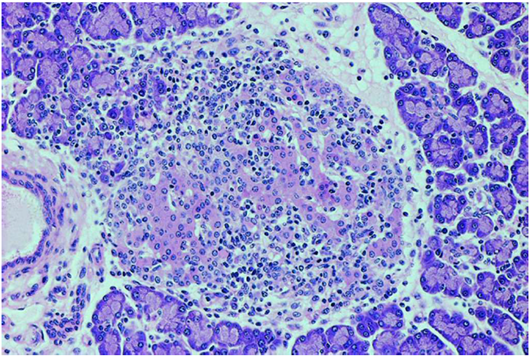

Patient died for cardiac tamponade from metastatic hemopericardium, after 36 months from the oncological diagnosis. It followed an autoptic investigation: the pancreatic histology was indicative for typical insulitis and pancreas beta-cells expressed PDL1 in 42% of specific endocrine tissue (Figure 1-2).

Figure 2 The pancreatic islets were infiltrated by numerous lymphocytes like a typical picture of immune-mediated insulitis.

We show a histologic image of a typical insulitis related to use of a checkpoint inhibitor like the insulitis in autoimmune type 1 diabetes. The expression of PD-L1 on beta pancreatic cells may be implicated in immunological tolerance and may induce an autoimmune process. Other cases of type 1 diabetes related to PD1/PDL1 checkpoint inhibitors are described in literature.12,13 The increasing use of these new drugs stimulates the publication of new guidelines for the identification and treatment of specific side effects.14 These side effects may compare in 7-11 weeks after the beginning of therapies with checkpoint inhibitors, but they also may develop after months or years, and may have a long duration. It’s important to identify these symptoms because the treatment is completely different from the conventional chemotherapy. In conclusion, immune checkpoint inhibitors (anti-CTLA-4 and anti-PDL-1) can induce the development of autoimmune diseases, among which autoimmune endocrinopathies (thyroiditis, adrenalite, hypophysitis, type 1 diabetes): therefore, before the beginning of the treatment, it’s important to take an accurate personal and familiar history, to control hormones and glycemia before, during and after treatment and, if possible, to valuate a screening antibodies panel in order to select patients at greater risk of developing an autoimmune diseases.